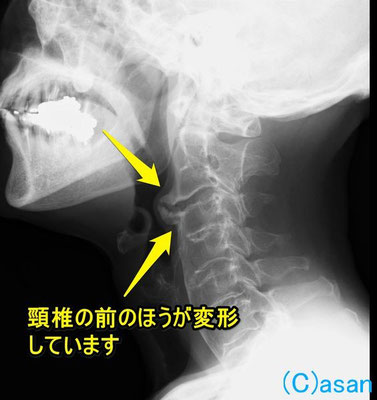

レントゲン写真で見ると、首の骨(頸椎)の前方がとげのように変形(骨棘)しているのがわかります。これは生まれつきではなく、年齢とともに出てきたものですが、気づいたのが最近になってということでしょう